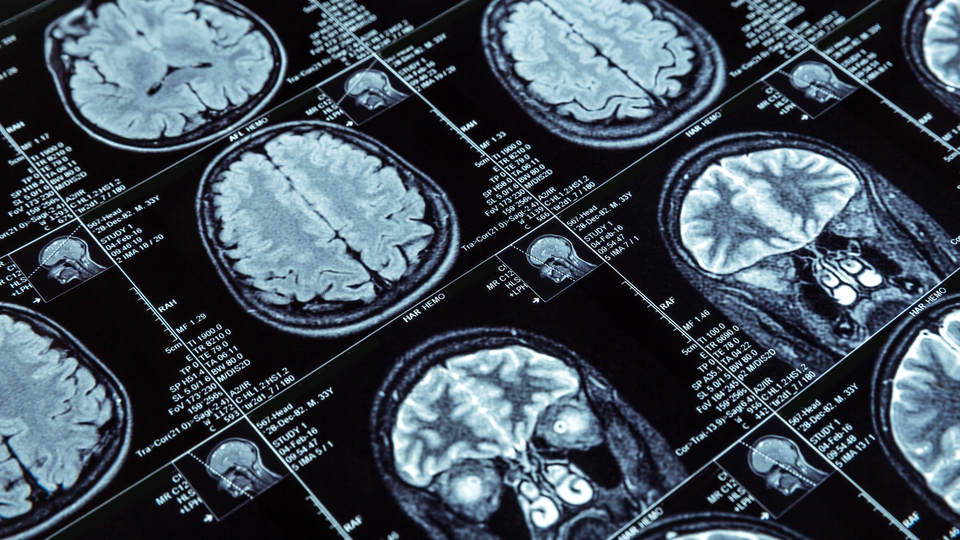

Beyin sağlığını koruma, beyinle ilgili hastalıklara karşı erken teşhis ve tedavinin önemi hakkında bilgi veren Topçuoğlu, "Beyin diğer organlardan biraz farklı. Beynimizde bulunan 86 milyar nöronun birbiriyle karşılıklı kurduğu çok iyi ilişki, bizi de biz yapıyor. Yürümenin, konuşmanın dışında sevgi, kaygı gibi duygularımız, gelecek planlarımız ayrıca kalp atışı, nefes alma gibi otonomik fonksiyonların tamamı beyin tarafından gerçekleştiriliyor" diye konuştu.

Covid-19'u ağır geçiren hastalarda bütün vücut gibi beynin de bu süreçten etkilendiğini ama farklı şiddetli hastalıklarda da aynı durumun görülebildiğini belirten Topçuoğlu, "Beynimizdeki 86 milyar nöron içerisinde Covid-19'un içeriye girişini sağlayacak reseptörler bulunmuyor. Fakat virüs, bu bölgedeki damarlar ve destek hücrelerinde bulunabiliyor. Dolayısıyla beyin indirekt şekilde etkileniyor ama beyin iltihabı ve diğer açılardan bir etkilenme söz konusu değil" dedi.